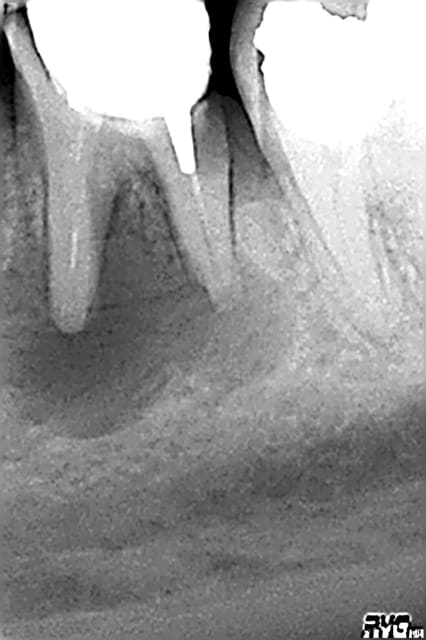

08/11/2008 à 14h03

puis des fois ça parait bien...et c'est l'extraction

radios: Mai/ aout/ octobre

tonio

10/11/2008 à 14h36

ploc écrivait:

--------------

> puis des fois ça parait bien...et c'est l'extraction

> radios: Mai/ aout/ octobre

pourquoi n'as-tu pas envisagé d'emblée l'extraction sur cette dent? l'échec était prévisible malgré la qualité de ton traitement endo, non?

tu vas me dire, facile à dire a posteriori, c'est vrai.

quand on veut sauver une dent porteuse d'une LIPOE, il y a d'autres paramètres à prendre en compte que la lésion, comme le délabrement de la dent ou encore l'accessibilité aux canaux.

Dans ton cas, force est de constater que l'accessibilité aux cas n'a pas posé de problème.

Par contre, j'aurai extrait la dent pour les raisons suivantes:

- zone interradiculaire très fragile (voire perforée)

- carie sous gingivale à mi-hauteur sur la racine D

- délabrement coronaire conséquent voire total

- racines de petite taille, probablement résorbées par la LIPOE: donc faible appui pour le futur IC et difficulté de contrôle de la longueur de l'obturation du fait de l'absence de cône apical.

ploc

10/11/2008 à 19h28

tonio écrivait:

---------------

>

> Par contre, j'aurai extrait la dent pour les raisons suivantes:

> - zone interradiculaire très fragile (voire perforée)

non,vérifié après extraction

> - carie sous gingivale à mi-hauteur sur la racine D

au 1/3

> - délabrement coronaire conséquent voire total

certes mais j'ai fait pire

> - racines de petite taille, probablement résorbées par la LIPOE: donc faible> appui pour le futur IC et difficulté de contrôle de la longueur de l'obturation

> du fait de l'absence de cône apical.

dommage,je n'ai pas eu le reflexe de prendre la dent en photo sur une compresse(vu en urgence evidemment)

la dent n'était pas fracturée,l'obturation(gutta condensée) vraiment bien

par contre c'est vrai ,racines courtes et surtout aucune recuperation osseuse

le curetage et comblement ont été plus longs que l'extract

il existait un paramètre subjectif et affectif:petit,il a partagé le mme cheval que ma fille et lui fait couler maintenant des jours heureux au pré:)

moniteur,il n'a pas trop de sous

je partais:mon rempla à qui je refile les endos difficiles qd il vient(je suis une titulaire qui aime les endos de son remplaçant et lui fait confiance:) a tenté, pr me faire plaisir,bien que sceptique(moi aussi)

hors du temps et de l'argent,on n'avait rien à perdre et le patient aurait pu gagner qqes années